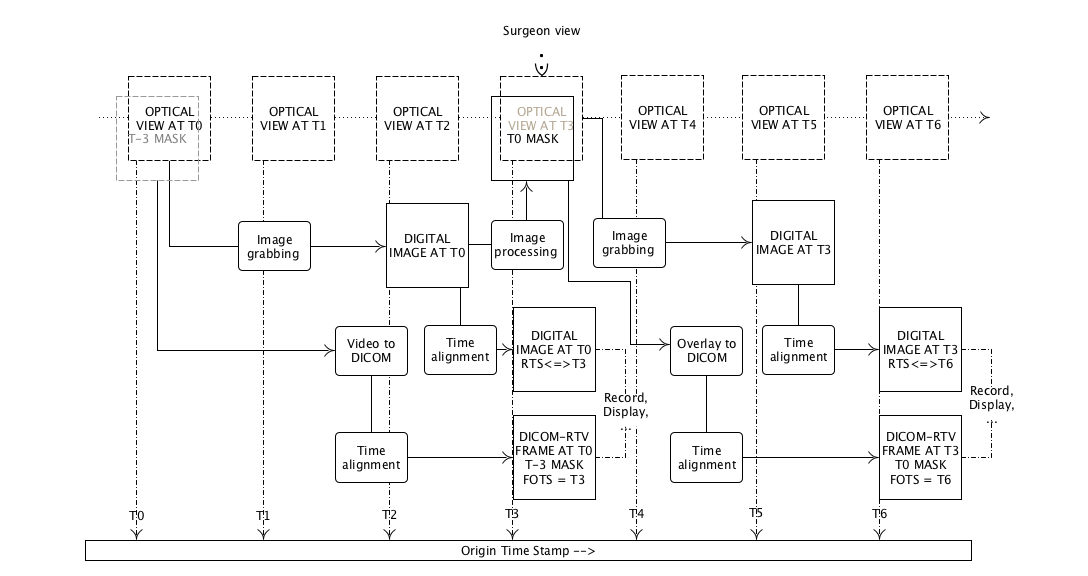

- PPPP.7. Example of DICOM Real-Time Video Implementation

- PPPP.8. Storage Considerationa

- PPPP.9. Example of Engineering Implementation

- PPPP.20. Transmitting a Stereo Video